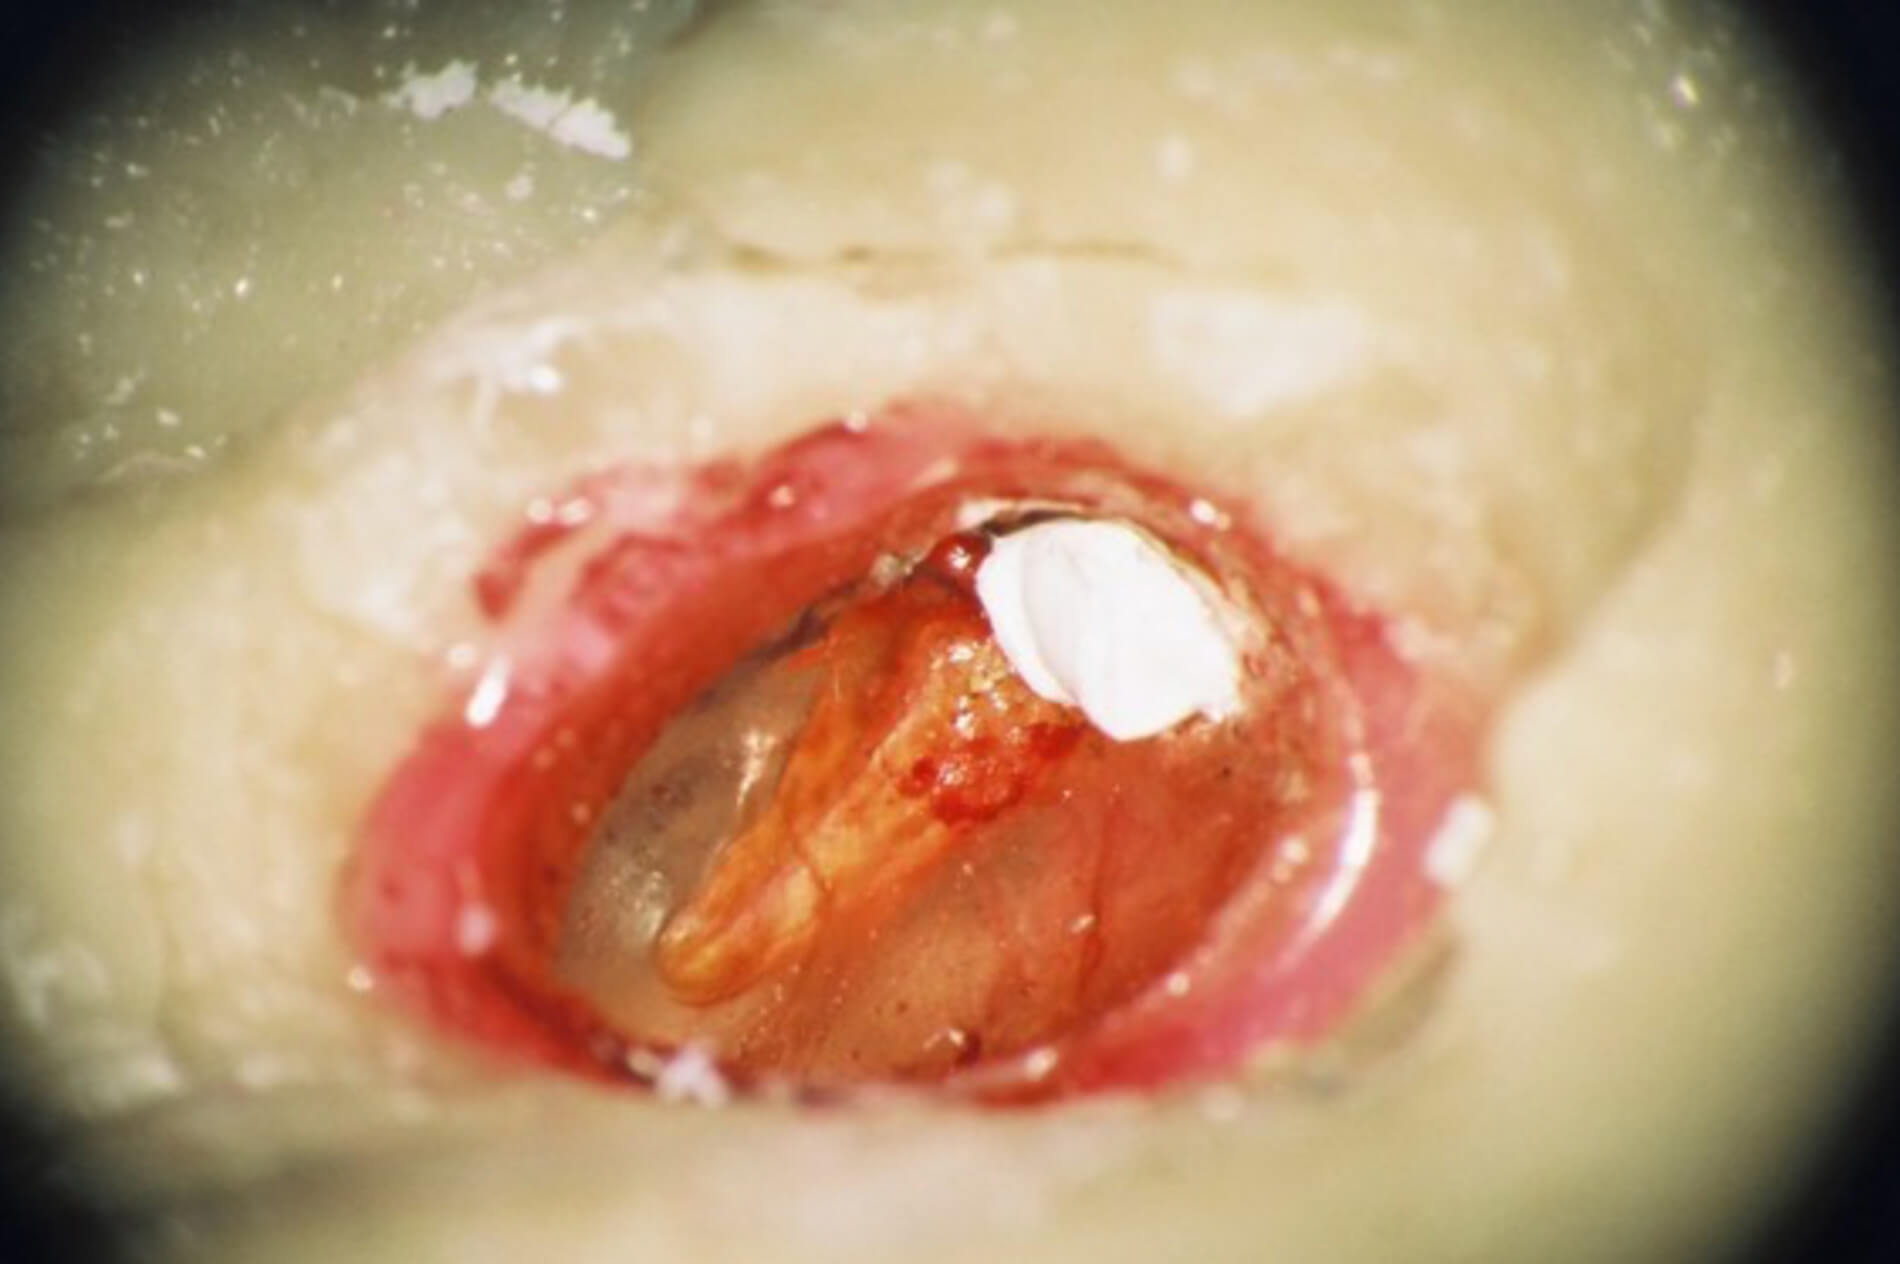

He also became aware from the recent literature that his bones had certain advantages over the newer simulation technologies in relation to the tympanic membrane, ossicles and the facial nerve. Moreover, a perforation of the tympanic membrane, or a cholesteatoma can be introduced to his bones to provide a challenge to the young surgeon.